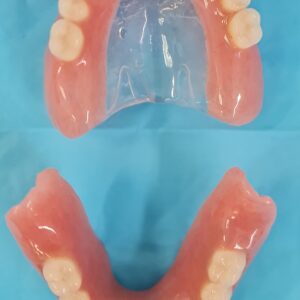

There are two types of implant dentures: bar-retained and ball-retained. In both cases, the denture will be made of an acrylic base that will look like gums. Porcelain or acrylic teeth that look like natural teeth are attached to the base. Both types of dentures need at least two implants for support.

- Ball-retained dentures (most common) — Each implant in the jawbone holds a metal attachment that fits into another attachment on the denture. In most cases, the attachments on the implants are ball-shaped (“male” attachments), and they fit into sockets (“female” attachments) on the denture. In some cases, the denture holds the male attachments and the implants hold the female ones.

- Bar-retained dentures — A thin metal bar that follows the curve of your jaw is attached to the implants that have been placed in your jawbone. Clips or other types of attachments are fitted to the bar, the denture or both. The denture fits over the bar and is securely clipped into place by the attachment